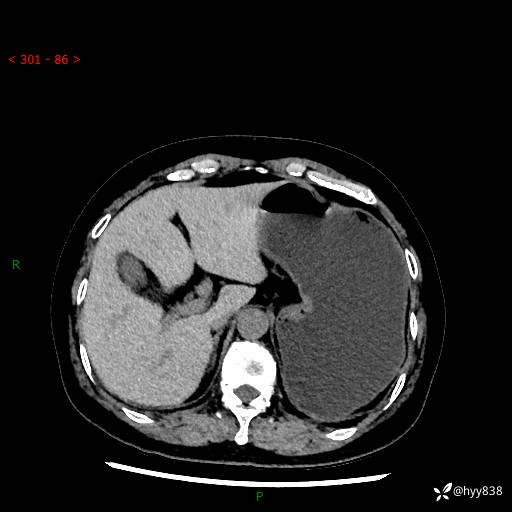

辅助检查:CT

胃CT平扫+增强(动脉期+静脉期)

三期CT值:46hu 58hu 75hu